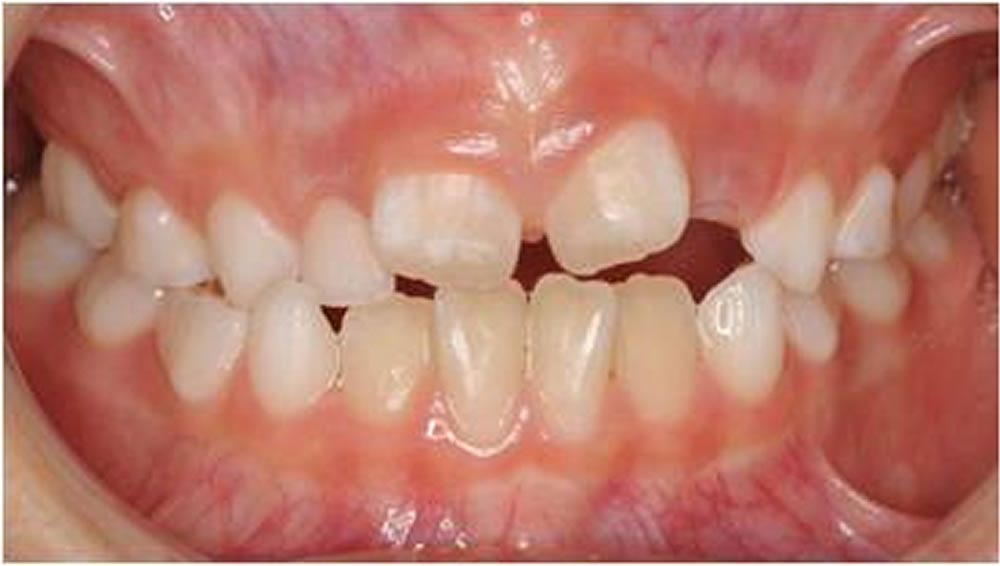

BiVi歯科・矯正歯科で実施した小児矯正の治療例をご紹介

▼当院で実際に行った小児矯正治療の症例をご紹介します。